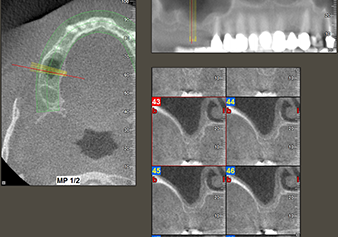

49-летняя пациентка, некурящая и не имеющая ничего примечательного в общей истории болезни, была направлена в нашу хирургическую стоматологическую клинику для хирургического удаления зуба 16 и последующей имплантации. После удаления зуба пациентка перенесла синусит в легкой форме, в результате чего мы сначала выждали шесть месяцев перед проведением операции. Остаточная высота кости при запланированном положении имплантата составляла 3-4 мм (рис. 1 и 2).